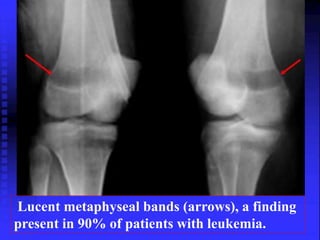

Lucent metaphyseal bands (arrows), a finding

present in 90% of patients with leukemia.